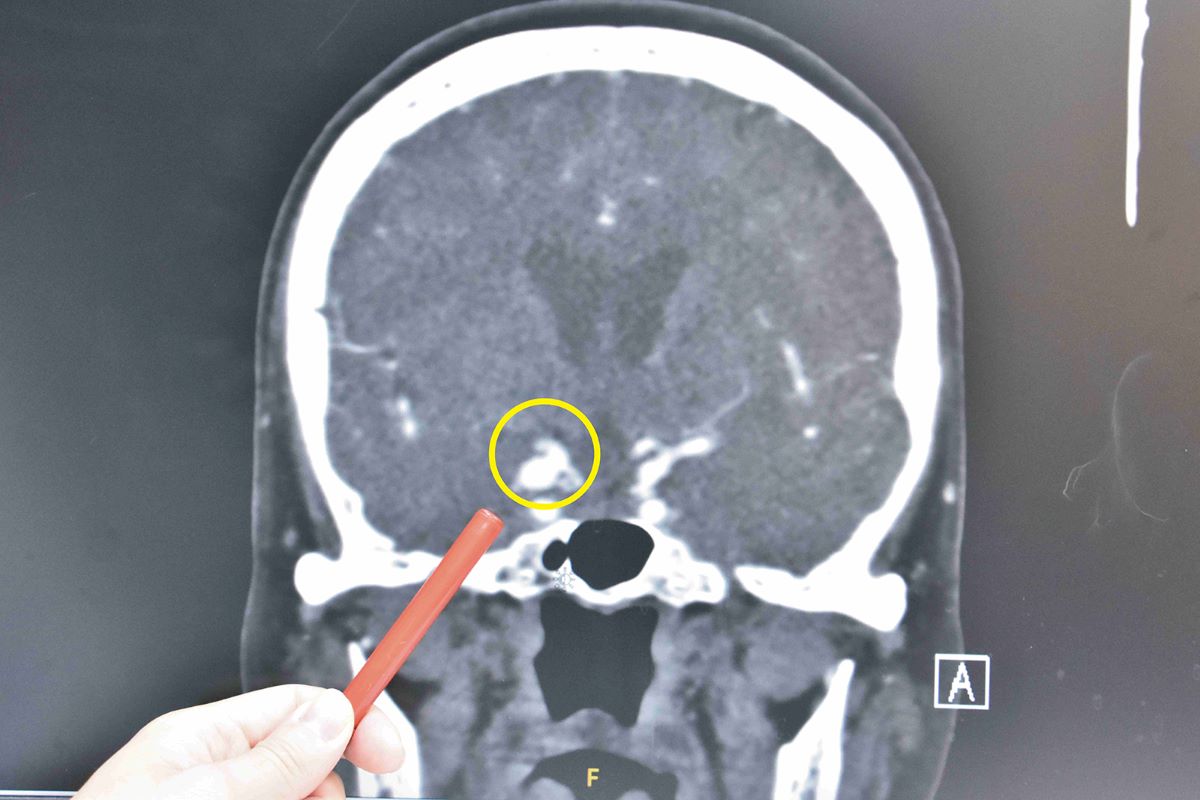

▲曾姓婆婆的動脈瘤有壓迫到視神經或動眼神經,在破裂出血造成昏迷前及時發現。(圖/彰基提供)

曾姓婆婆頭暈目眩雙眼複視、畏光長達1個月,在眼科診所拿藥滴眼藥水依然沒有改善,一周後忽然右眼皮下垂,完全睜不開,經眼科轉診至神經外科門診,在門診時發現婆婆右眼皮下垂無力,右眼球只能朝外轉動,不能朝內轉也無法向上轉動,立即將病患安排緊急電腦斷層血管攝影,發現竟是長達8mm的右側顱內後交通動脈瘤,造成動眼神經壓迫,經安排至手術室進行開顱動脈瘤夾除手術,術後住院7天即出院返家休養。術後一個月右眼皮漸漸恢復可以張開,右眼轉動也漸漸恢復正常,畏光與複視重影症狀也漸漸改善。

彰基神經外科主治醫師郭明錡表示,「顱內動脈瘤」名稱上雖然有個「瘤」字,卻不是惡性的東西,不會擴散或是轉移,無法由抽血的方式來篩檢得知。動脈瘤是腦血管側邊或是末端的不正常膨大,形成原因是血流的衝擊使得薄弱的血管壁向外膨出形成。顱內動脈瘤是潛伏性的殺手,絕大部分患者終其一生是無症狀的,除了少數如曾婆婆的動脈瘤有壓迫到視神經或動眼神經,在破裂出血造成昏迷前及時發現,可以早期處理,大部分的病患往往是已經破裂而造成劇烈頭痛、意識不清才緊急送醫處理。